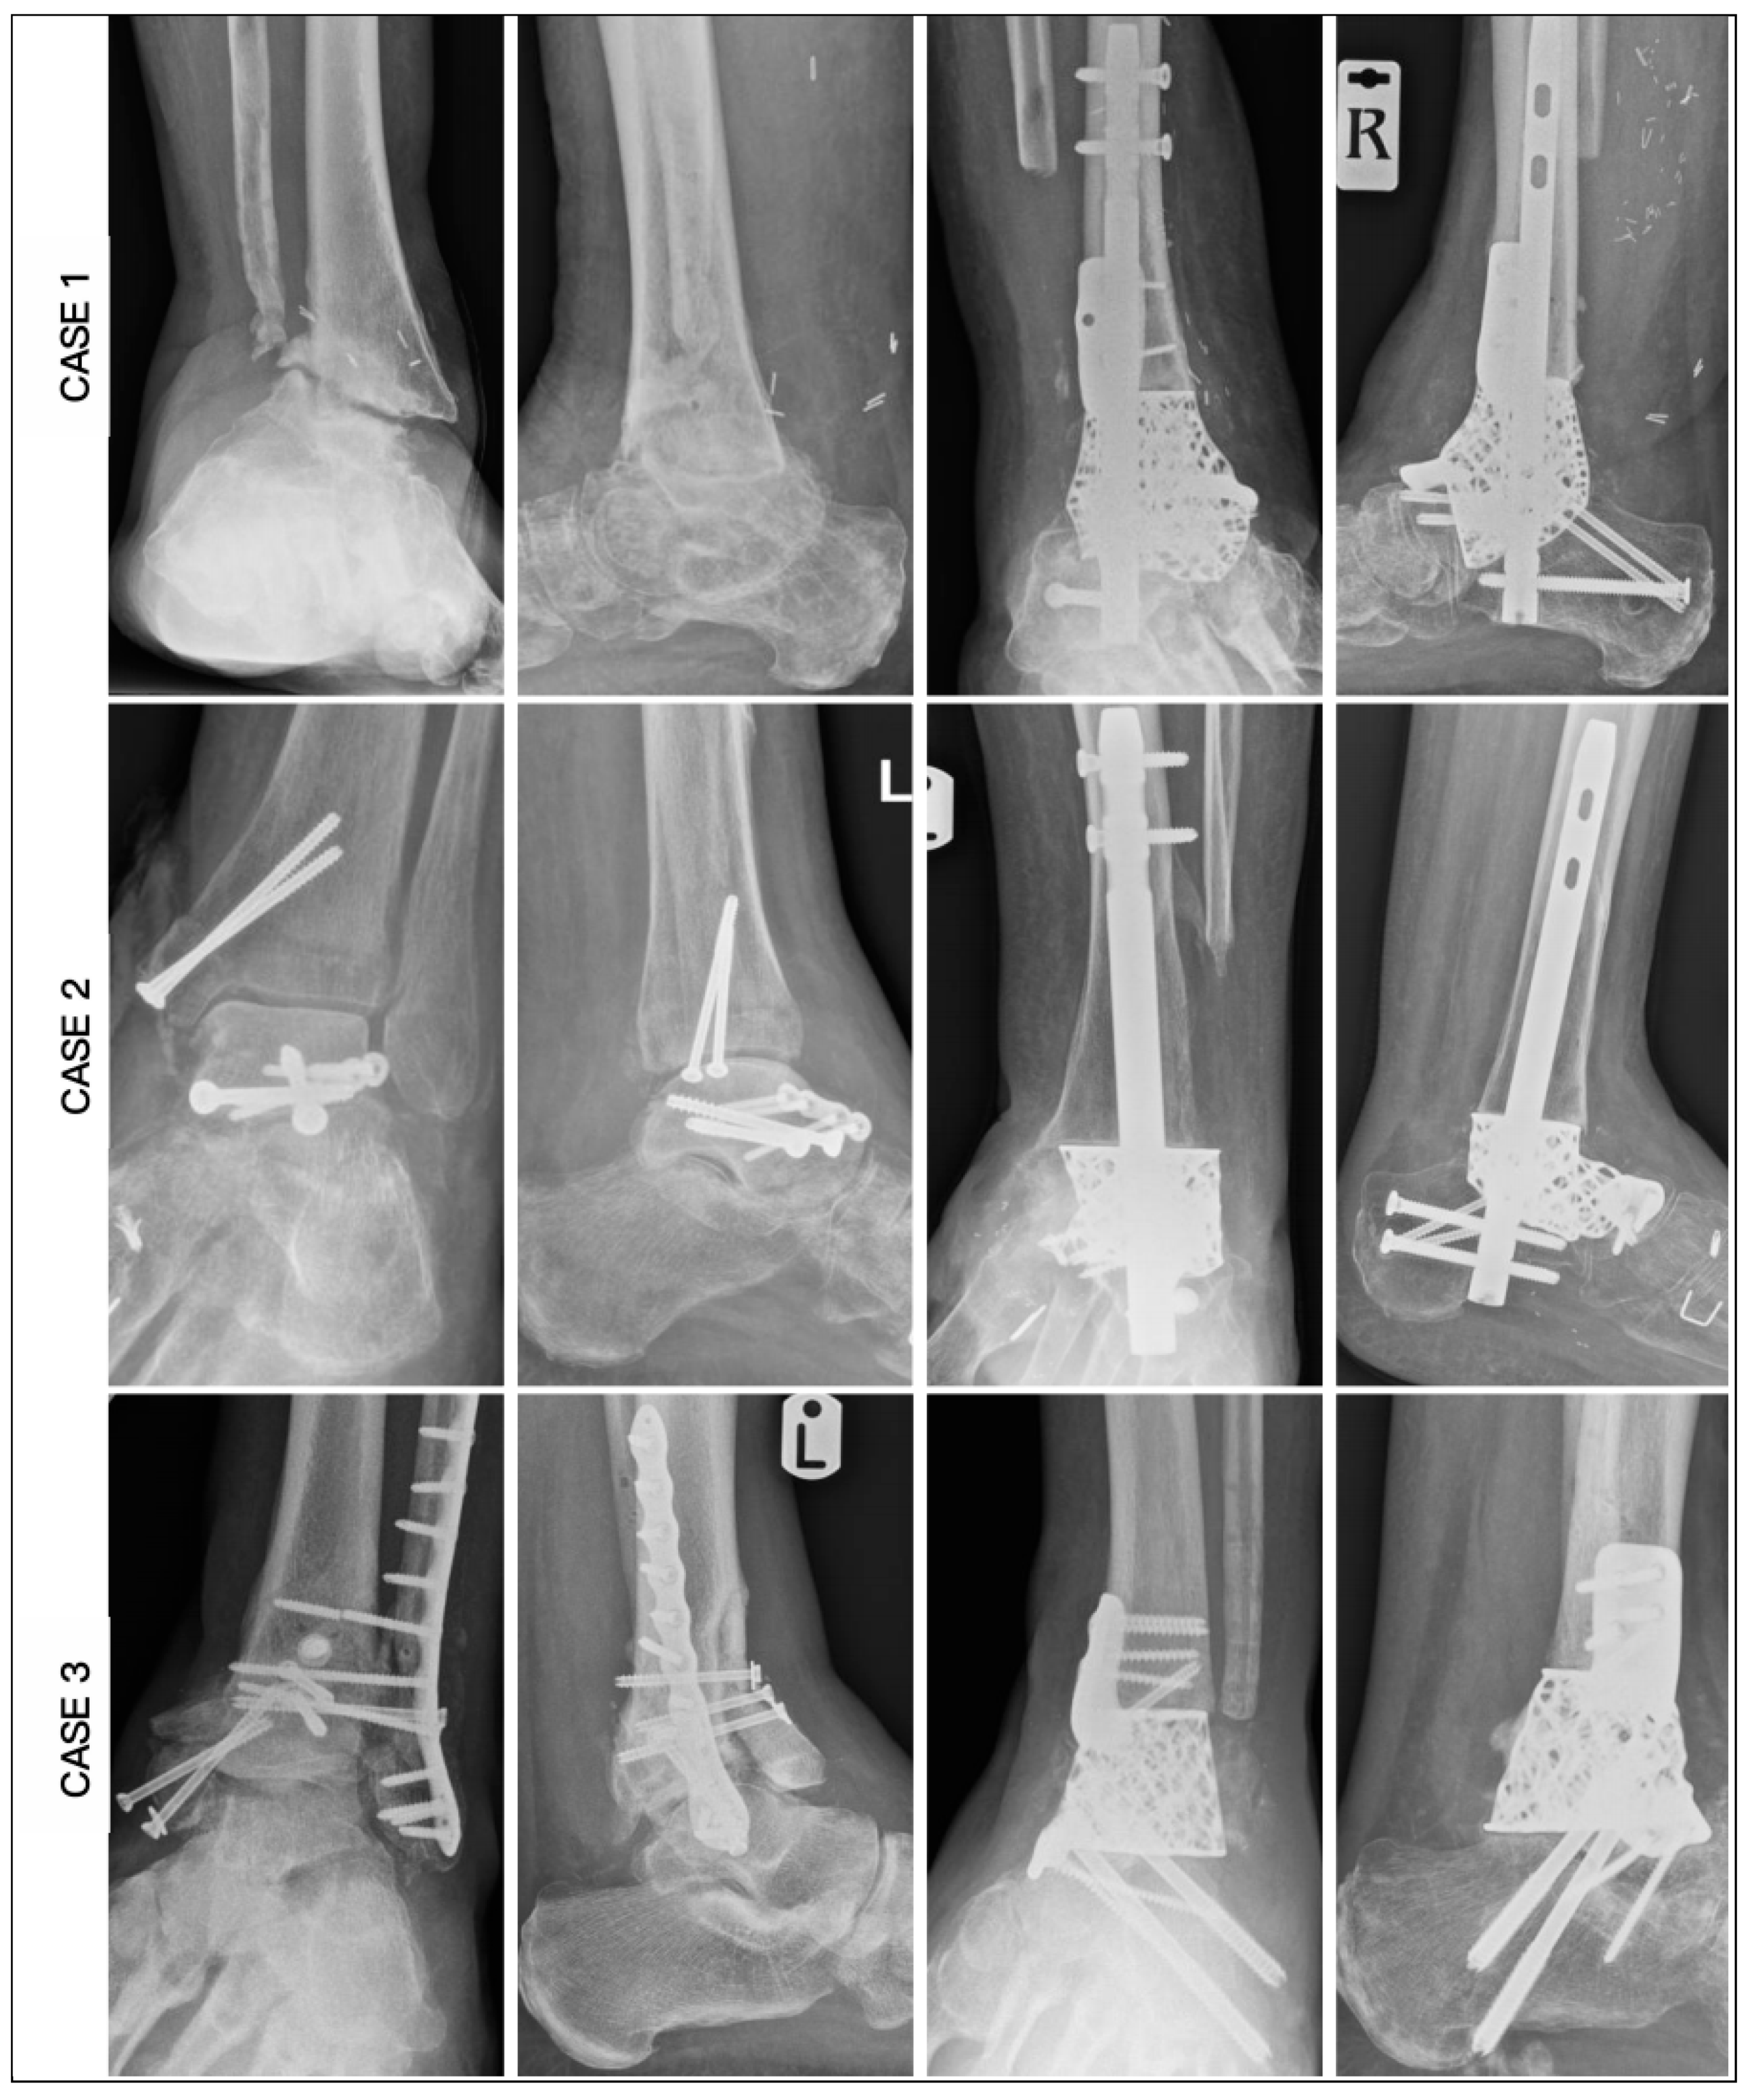

3. Results

| CASE | 1 | 2 | 3 | 4 | 5 | 6 |

|---|---|---|---|---|---|---|

| Age | 62 | 59 | 60 | 60 | 78 | 67 |

| Diagnosis | OM | OM | OM | AVN | AVN | AVN |

| Smoking | No | Yes | Yes | No | Yes | No |

| BMI | 26.5 | 27.4 | 27.4 | 28.2 | 32.1 | 35.4 |

| Medical | Nil | IHD, CKD, PAD | CKD | CKD, PAD | DM | IHD, DM, CKD, CN |

| HbA1c | 36 | 39 | 39 | 41 | 49 | 70 |

| CRP | 8 | 7 | 16 | 9 | 10 | 6 |

| Hb (g/L) | 113 | 105 | 132 | 146 | 113 | 114 |

| Past surgery | 5 | 3 | 3 | 0 | 1 | 0 |

| Modification | Tibial and Navicular Flange, Nail | Navicular Flange, Nail | Tibial and Navicular Flange | Navicular Flange, Nail | Nail | Articulating Navicular Extension, Tibial Flange, Nail |

| Duration of surgery (min) | 255 | 220 | 162 | 210 | 190 | 205 |

| Wound Healing (days) | 42 | 40 | 20 | 29 | 32 | 45 |

| Union (weeks) | 25 | 19 | 16 | 14 | 27 | 20 |

| Ambulation (weeks) | 28 | 21 | 18 | 16 | 29 | 22 |